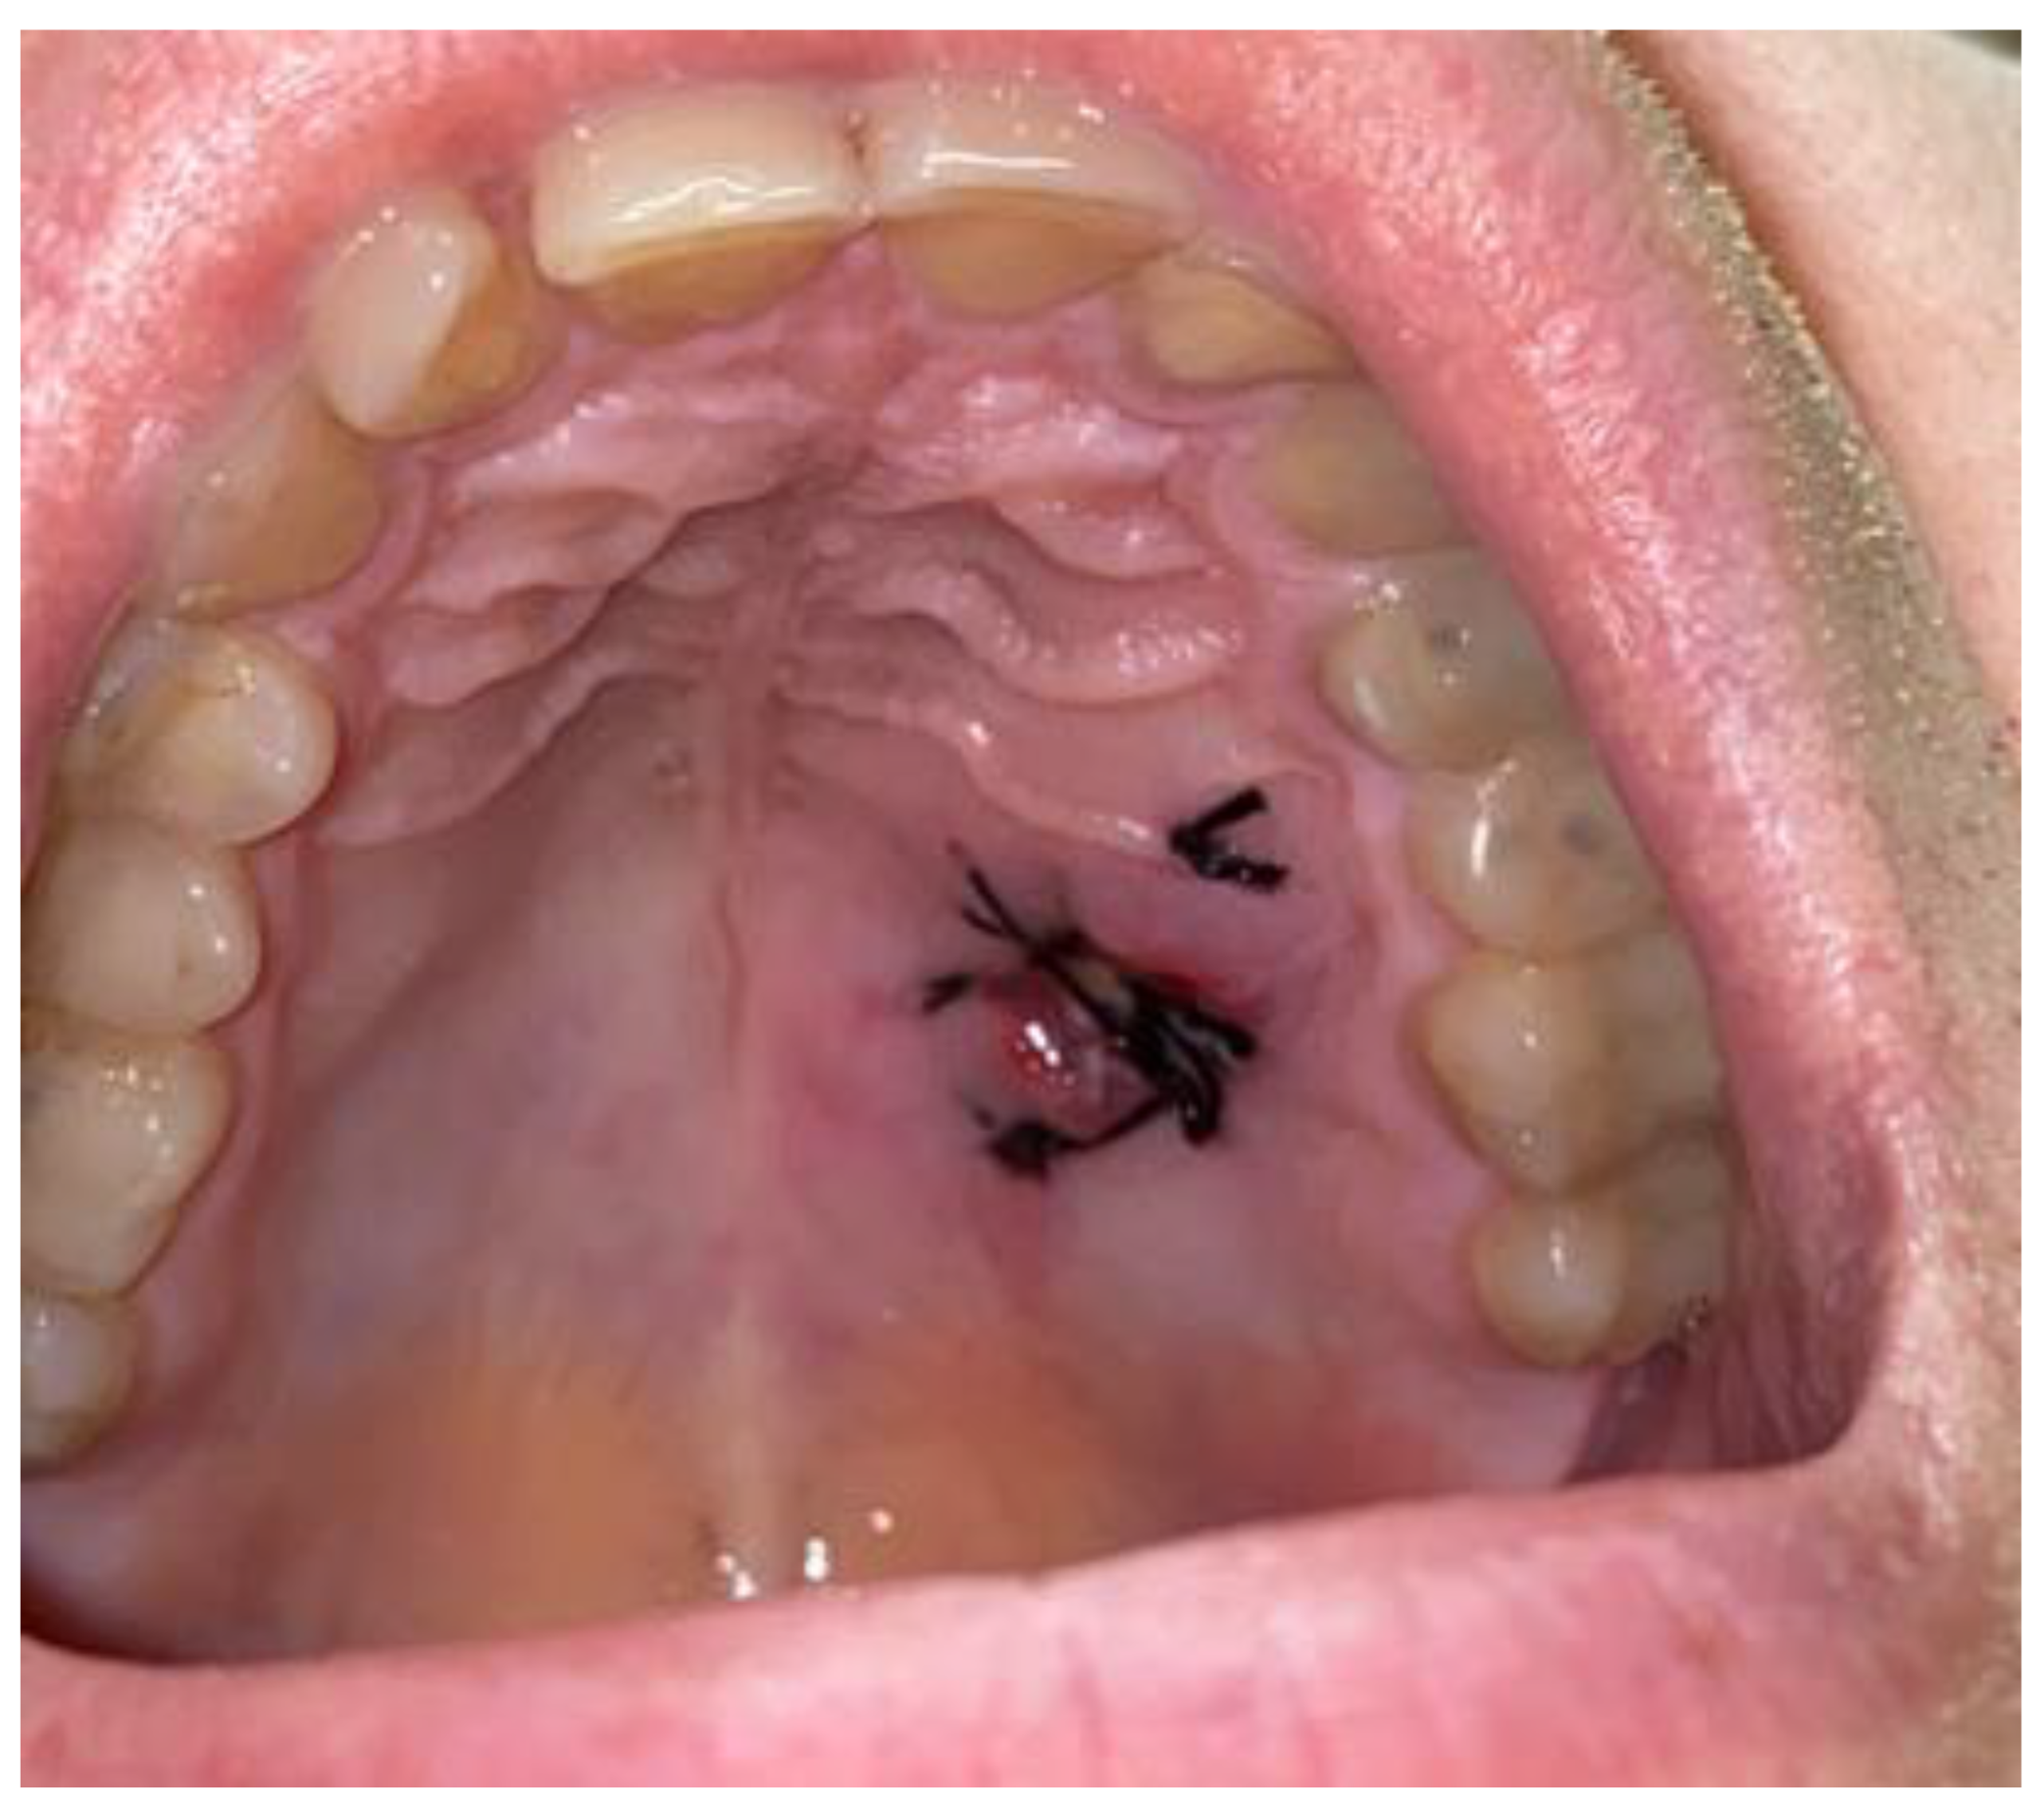

2. Case Description

- Excisional biopsy and gathering a good amount of studied tissue is the most effective way to investigate the nature of any oral neural tumor.